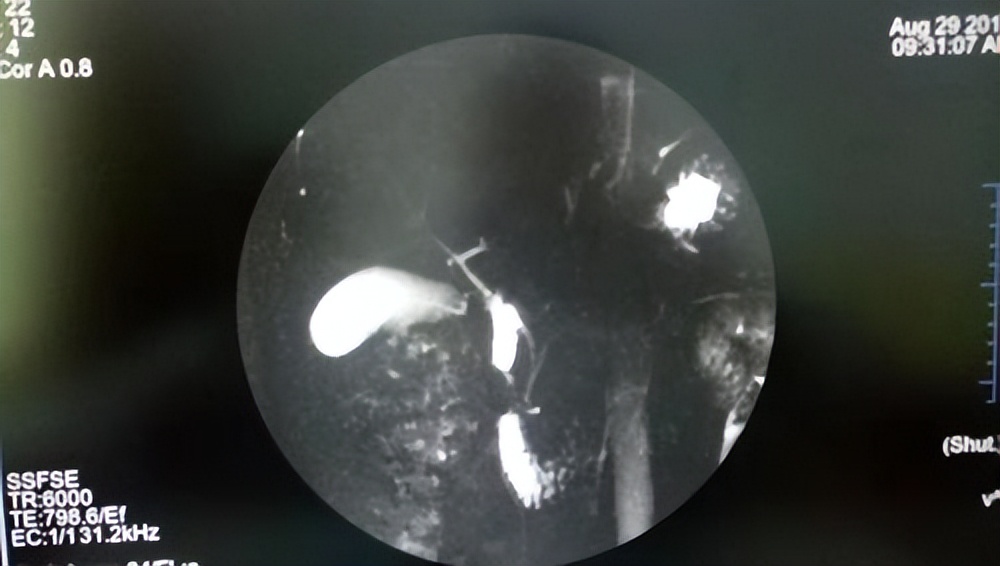

MRCP

MRCP已经成为公认的诊断性ERCP的替代方法。在迄今发表的大多数研究中,MRCP相对于ERCP,其灵敏度和特异度为90%或更高,但也有少数研究显示MRCP相对ERCP的灵敏度低于此。

一项研究表明,对于直径<5mm的结石,MRCP的灵敏度从100%降至71%。 以ERCP为参考标准的研究证实,MRCP诊断胆总管结石的能力虽然总体良好,但受结石直径的影响。 MRCP不依赖于操作者技术,可完整显示肝内外管系统及胰管,但容易漏诊较小的结石。尽管有良好的效果,但由于价格昂贵,其不作为常规检查推荐,此外不适用于体内有金属及幽闭恐惧症等病人。